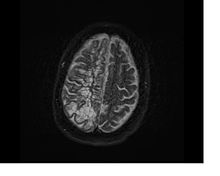

Axial fat suppressed T2 weighted MRI image in the same patient as above demonstrating extensive dilated Type 2 perivascular spaces in the right hemisphere